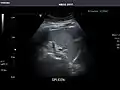

Spleen: Normal in size.